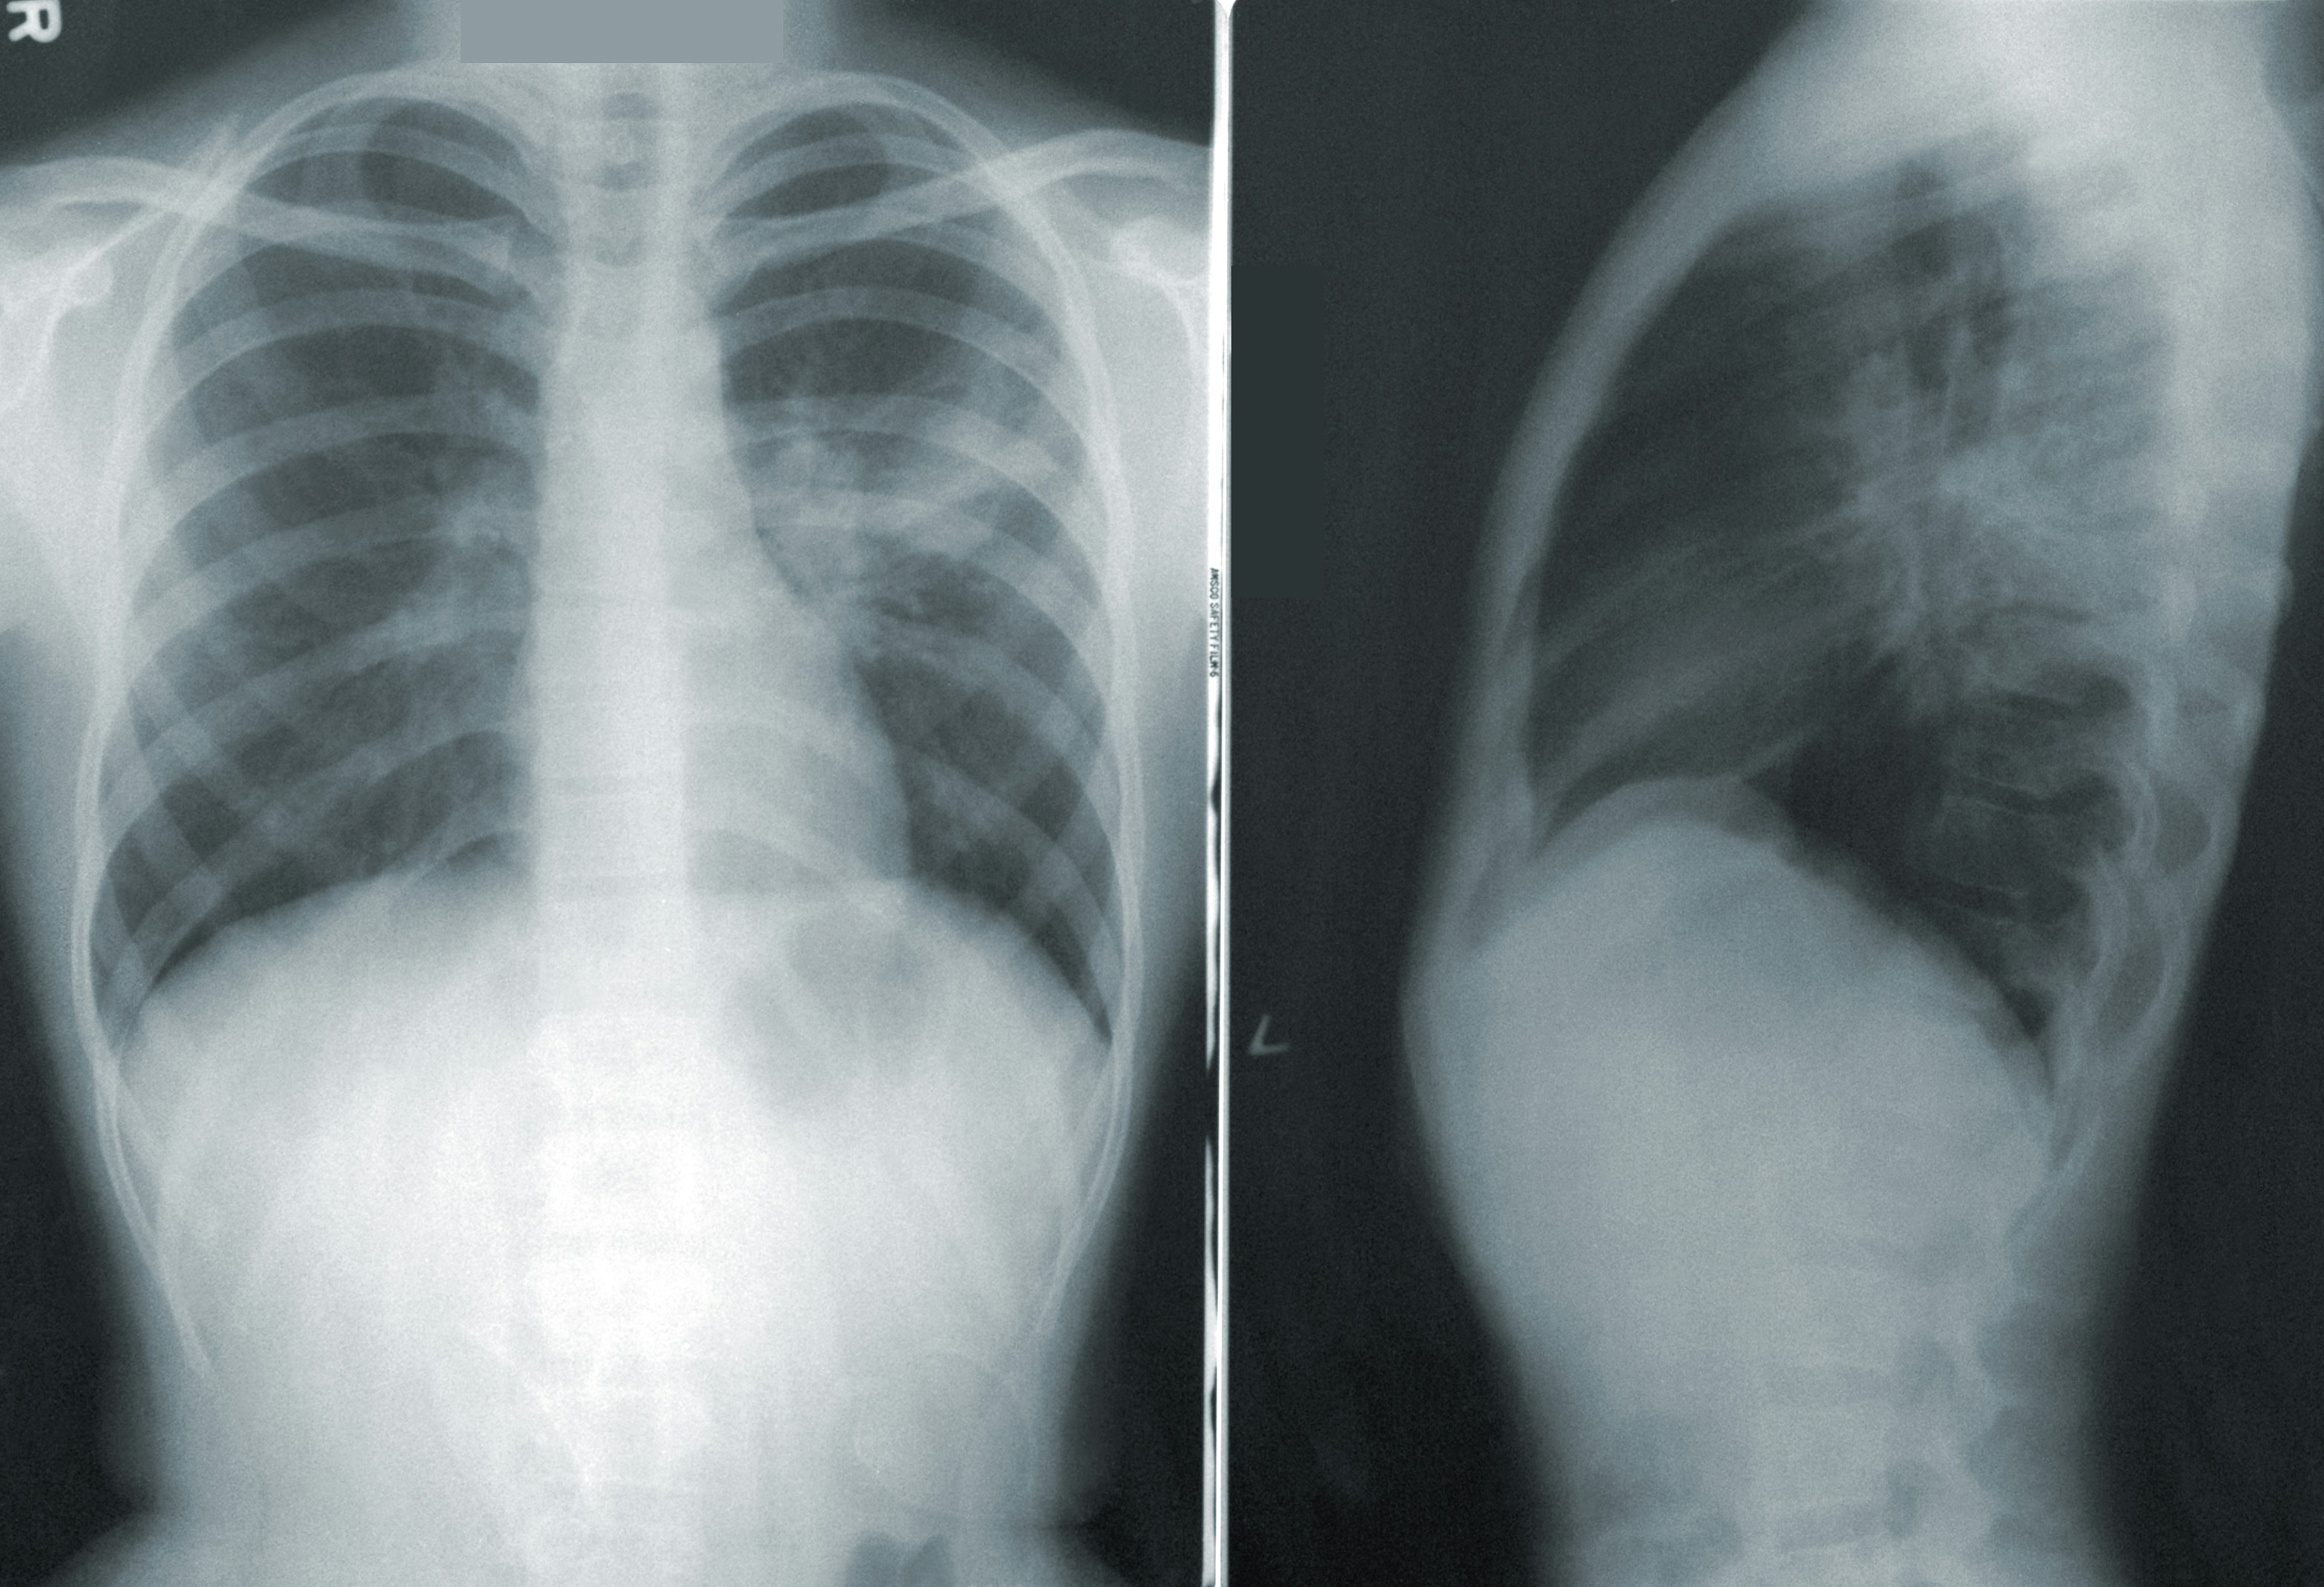

Lung Cancer: Remains one of the most common and deadly cancers both globally and in Southeast Asia, including Singapore. According to the Singapore Cancer Registry Annual Report 2022, lung cancer accounts for a significant proportion of cancer diagnoses and continues to be associated with high mortality, largely because many cases are detected only at advanced stages.

The World Health Organization also highlights that lung cancer is the leading cause of cancer deaths worldwide, while regional data show that it remains among the top five cancers in Southeast Asia, contributing substantially to cancer-related deaths (WHO, 2023; The Lancet Regional Health – Southeast Asia, 2024; Singapore Cancer Registry Annual Report 2022).

Lung cancer arises when epithelial cells in the airways accumulate damage from tobacco smoke, air pollutants or workplace toxins. Non-small cell lung cancer accounts for approximately 85% of cases, with small-cell lung cancer comprising most of the remainder . Symptoms like chronic cough or breathlessness often appear late, and in Singapore nearly half of non–small cell lung cancers (NSCLC) occur in never-smokers . Low-dose CT screening is currently recommended only for individuals aged 55–74 with a heavy smoking history (30 pack-years or more, smoking within the past 15 years); patients with a strong family history of lung cancer should also discuss screening options with a licensed healthcare professional.

Diagnosis begins with a patient history and physical exam to gather symptoms and risk factors. Blood tests look for abnormal values or tumour markers. Imaging scans (CT, MRI, PET) provide detailed internal pictures to locate masses. Biopsy, where a small tissue sample is examined under a microscope, to determine if one has cancer.

Screening programmes—such as mammography for breast cancer, Pap smears for cervical cancer, colonoscopy for colorectal cancer and low-dose CT scans for lung cancer—detect early-stage disease when treatment is most effective.